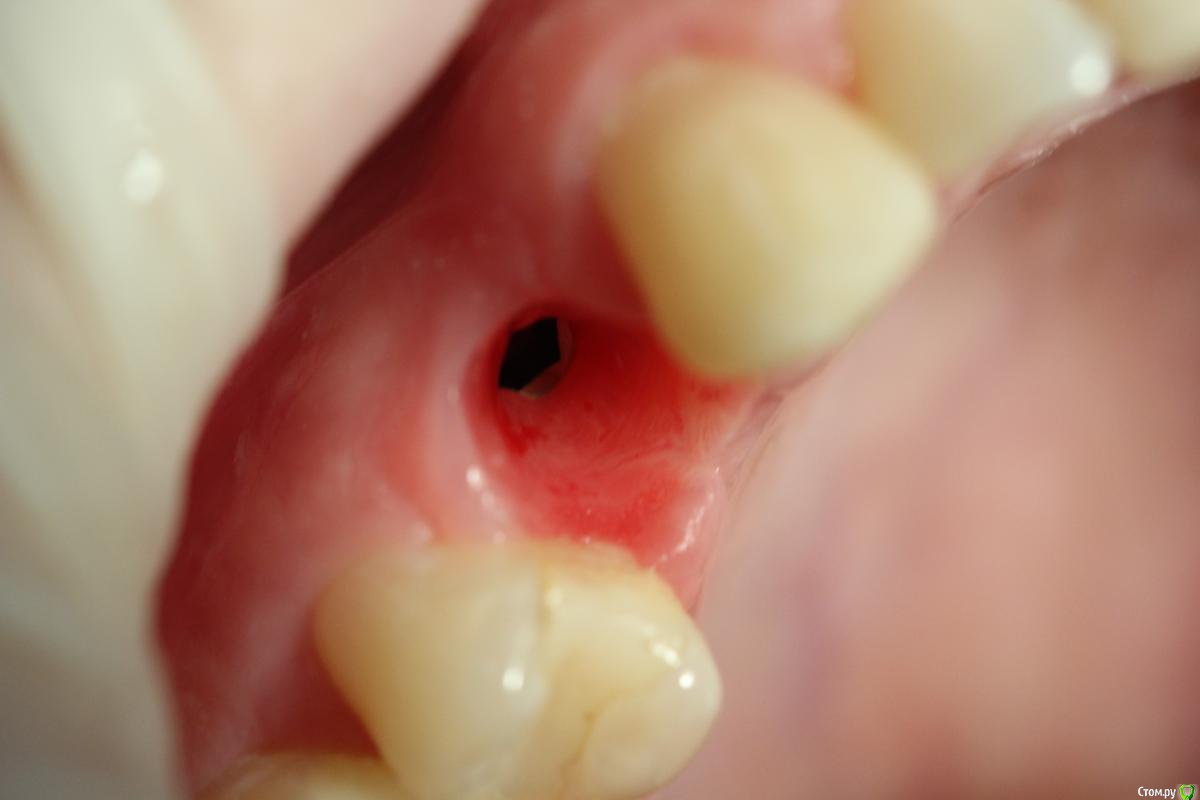

Ibulat_1986 Опубликовано 22 марта, 2016 Поделиться Опубликовано 22 марта, 2016 в первую очередь надо понять, индивидуальные формирователи нужны Вам для вызревание профиля прорезывания? Если формирователь Вам нужен при одномоментной имплантации после удаления в боковом отделе, то можно индивидуализировать с помощью жидкотекучего композита стандартный формирователь по форме лунки удаленного зубы. Ежели работа ведется во фронте, то временная коронка позволит Вам удобнее и точнее сформировать десневой колодец Ссылка на комментарий